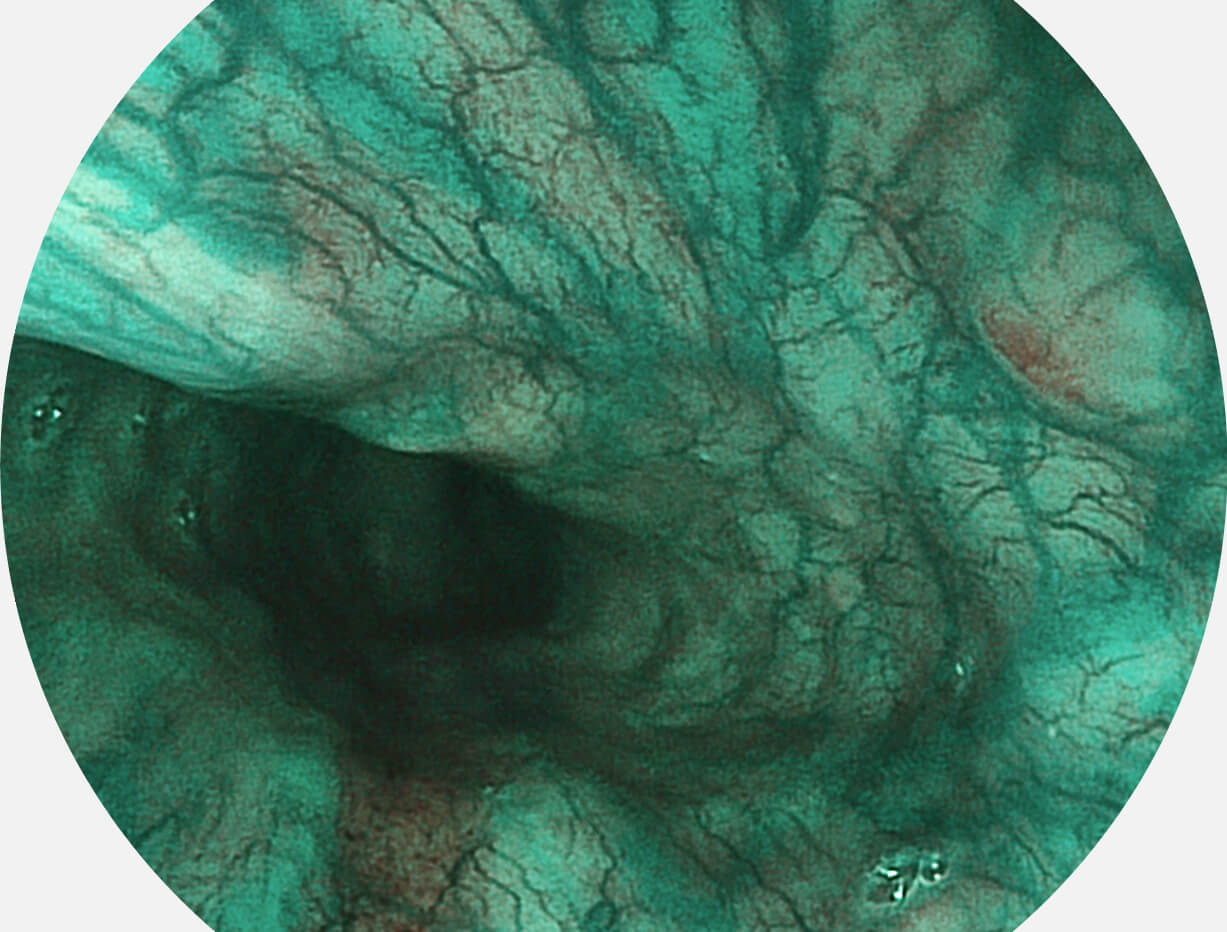

图像具有高亮度、高黏膜血管颜色对比度的特点,且不改变粘液、食物残渣、粪便的基本颜色,可在中远景下进行观察,助力消化道早期疾病的诊断。

• 白光图像 SFI图像